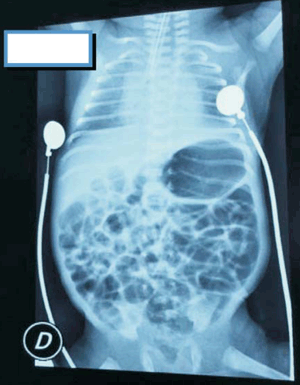

A los 20 días de vida, con edad posmenstrual de 31 semanas y 6 días, estando en crecimiento, ventilando al aire y con todo el aporte por vía enteral, se constató palidez cutáneo mucosa con FC 180-200 cpm, peso estacionario en la última semana. Se solicitó hemograma: hemoglobina (Hb) 8,4 g/dL y hematocrito (Hto) 26%, no se contó con valor de reticulocitos. Resto de las series normales. Con el planteo de anemia del prematuro con repercusión hemodinámica, se realizó transfusión de concentrado de glóbulos rojos (GR). A las 2 horas de comenzada la transfusión y habiendo pasado 20 ml (10 ml/kg) de GR, se constata apneas reiteradas, caídas de saturación de hasta 70% con bradicardia menor a 60 cpm, se realizó intubación orotraqueal y asistencia ventilatoria mecánica. Del examen físico se destacaba ausencia de hepatomegalia. No edema de párpados ni de partes blandas, no rush cutáneo. Se realizó ecocardiograma que evidenciaba ductus cerrado y buena función ventricular. Se detuvo transfusión de GR. Se realizó relevo infeccioso con procalcitonina (PCT) y proteína C reactiva (PCR) negativas, hemograma: Hb 12,6 g/dL, Hto 38,2%, glóbulos blancos 13.600/mm3, plaquetas 449.000/mm3. Sin evidencia de hemolisis. Radiografía de tórax: infiltrado bilateral difuso compatible con edema pulmonar (Figura 1). Se realizó ronda bacteriológica: hemocultivo, urocultivo, cultivo bacteriológico y virológico de líquido cefalorraquídeo (LCR), todos resultaron negativos. Cultivo de la sangre transfundida negativo. En las seis horas siguientes el paciente presentó varios episodios de distermias con Tax de hasta 37,2°. Se iniciaron ATB de segunda línea: vancomicina más meropenem, que se mantuvieron por siete días. A las 48 horas del evento mejoría clínico-gasométrica permitiendo la extubación programada, pasando a CPAP convencional. Se comunicó el evento adverso inmediatamente al equipo de hemoterapia. A los 35 días de vida, estando en crecimiento, se constató nuevamente anemia con repercusión hemodinámica, en acuerdo con hemoterapia se realizó segunda transfusión de GR a 20 ml/kg con previa administración de hidrocortisona a 5 mg/kg de manera empírica. La transfusión fue bien tolerada, sin complicaciones. La evolución posterior fue favorable, sin secuelas.

El diagnóstico de TRALI es clínico-radiológico. Clínicamente se presenta como un deterioro respiratorio agudo con hipoxemia dado por edema pulmonar no cardiogénico vinculado temporalmente a una transfusión de hemoderivados.

c) Infiltrados bilaterales pulmonares difusos en la radiografía de tórax.

En el caso clínico presentado se cumplen todos los criterios diagnósticos de TRALI propuestos. A las dos horas de iniciada la transfusión se constató hipoxemia evidenciada por saturación menor a 90%, necesidad de asistencia ventilatoria mecánica y una radiografía de tórax compatible con edema pulmonar. No había elementos clínicos ni ecocardiográficos de insuficiencia cardíaca. Este hecho descartó uno de los principales diagnósticos diferenciales que es la sobrecarga circulatoria aguda (TACO). La evolución del paciente fue favorable, como se observa en los casos de TRALI, con resolución en el curso de 72 horas.